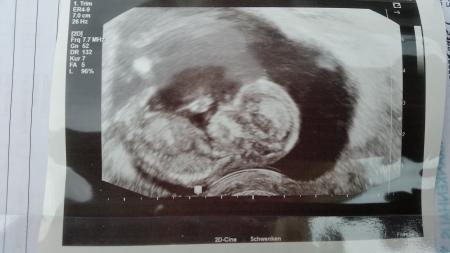

Mein Fa hat angerufen ich kann früher kommen. Bin nun wieder zurück und total verliebt... so ein süßes baby. Haben viele Organe gesehen und beide Herzklappen. Baby ist 6,7 cm ssl. Ach das War so toll. Bin so happy Und jetzt wieder 4 Wochen warten :-(

Glückwunsch, das klingt doch gut. Hast du ein Bild bekommen? Liebe Grüße.

Ja mit foto :-)

Bild zu